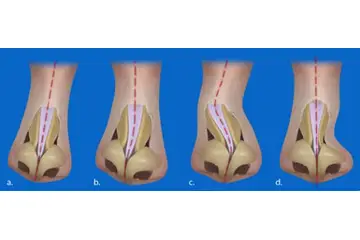

Burun Kıkırdak Eğriliği Belirtileri ve Tedavisi

Burun kıkırdak eğriliği, burun septumundaki bozuklukların neden olduğu rahatsız edici bir durumdur. Belirtileri arasında burun tıkanıklığı, baş ağrıları ve uyku apnesi yer alır. Tedavi seçenekleri, ilaçlardan cerrahi müdahalelere kadar değişir. Uzman görüşü, en uygun çözüm için önemlidir.

Burun Kıkırdak Eğriliği Belirtileri ve Tedavisi Burun kıkırdak eğriliği, burun septumunun (burun ortasındaki yapı) anormal bir şekilde eğrilmesi veya şekil bozukluğu olarak tanımlanabilir. Bu durum, bireylerin yaşam kalitesini etkileyen ve çeşitli sağlık sorunlarına yol açabilen önemli bir rahatsızlıktır. Burun kıkırdak eğriliği, genellikle doğuştan gelir, ancak travma veya yaralanmalar sonucu da gelişebilir. Burun Kıkırdak Eğriliğinin Belirtileri Burun kıkırdak eğriliği, birçok belirtiyle kendini gösterebilir. Bu belirtiler kişiden kişiye değişebilir, ancak genel olarak aşağıdaki semptomlar sıklıkla görülmektedir:

Tedavi Seçenekleri Burun kıkırdak eğriliği tedavisi, hastanın semptomlarına ve durumun ciddiyetine bağlı olarak değişiklik gösterir. Tedavi yöntemleri şunlardır: